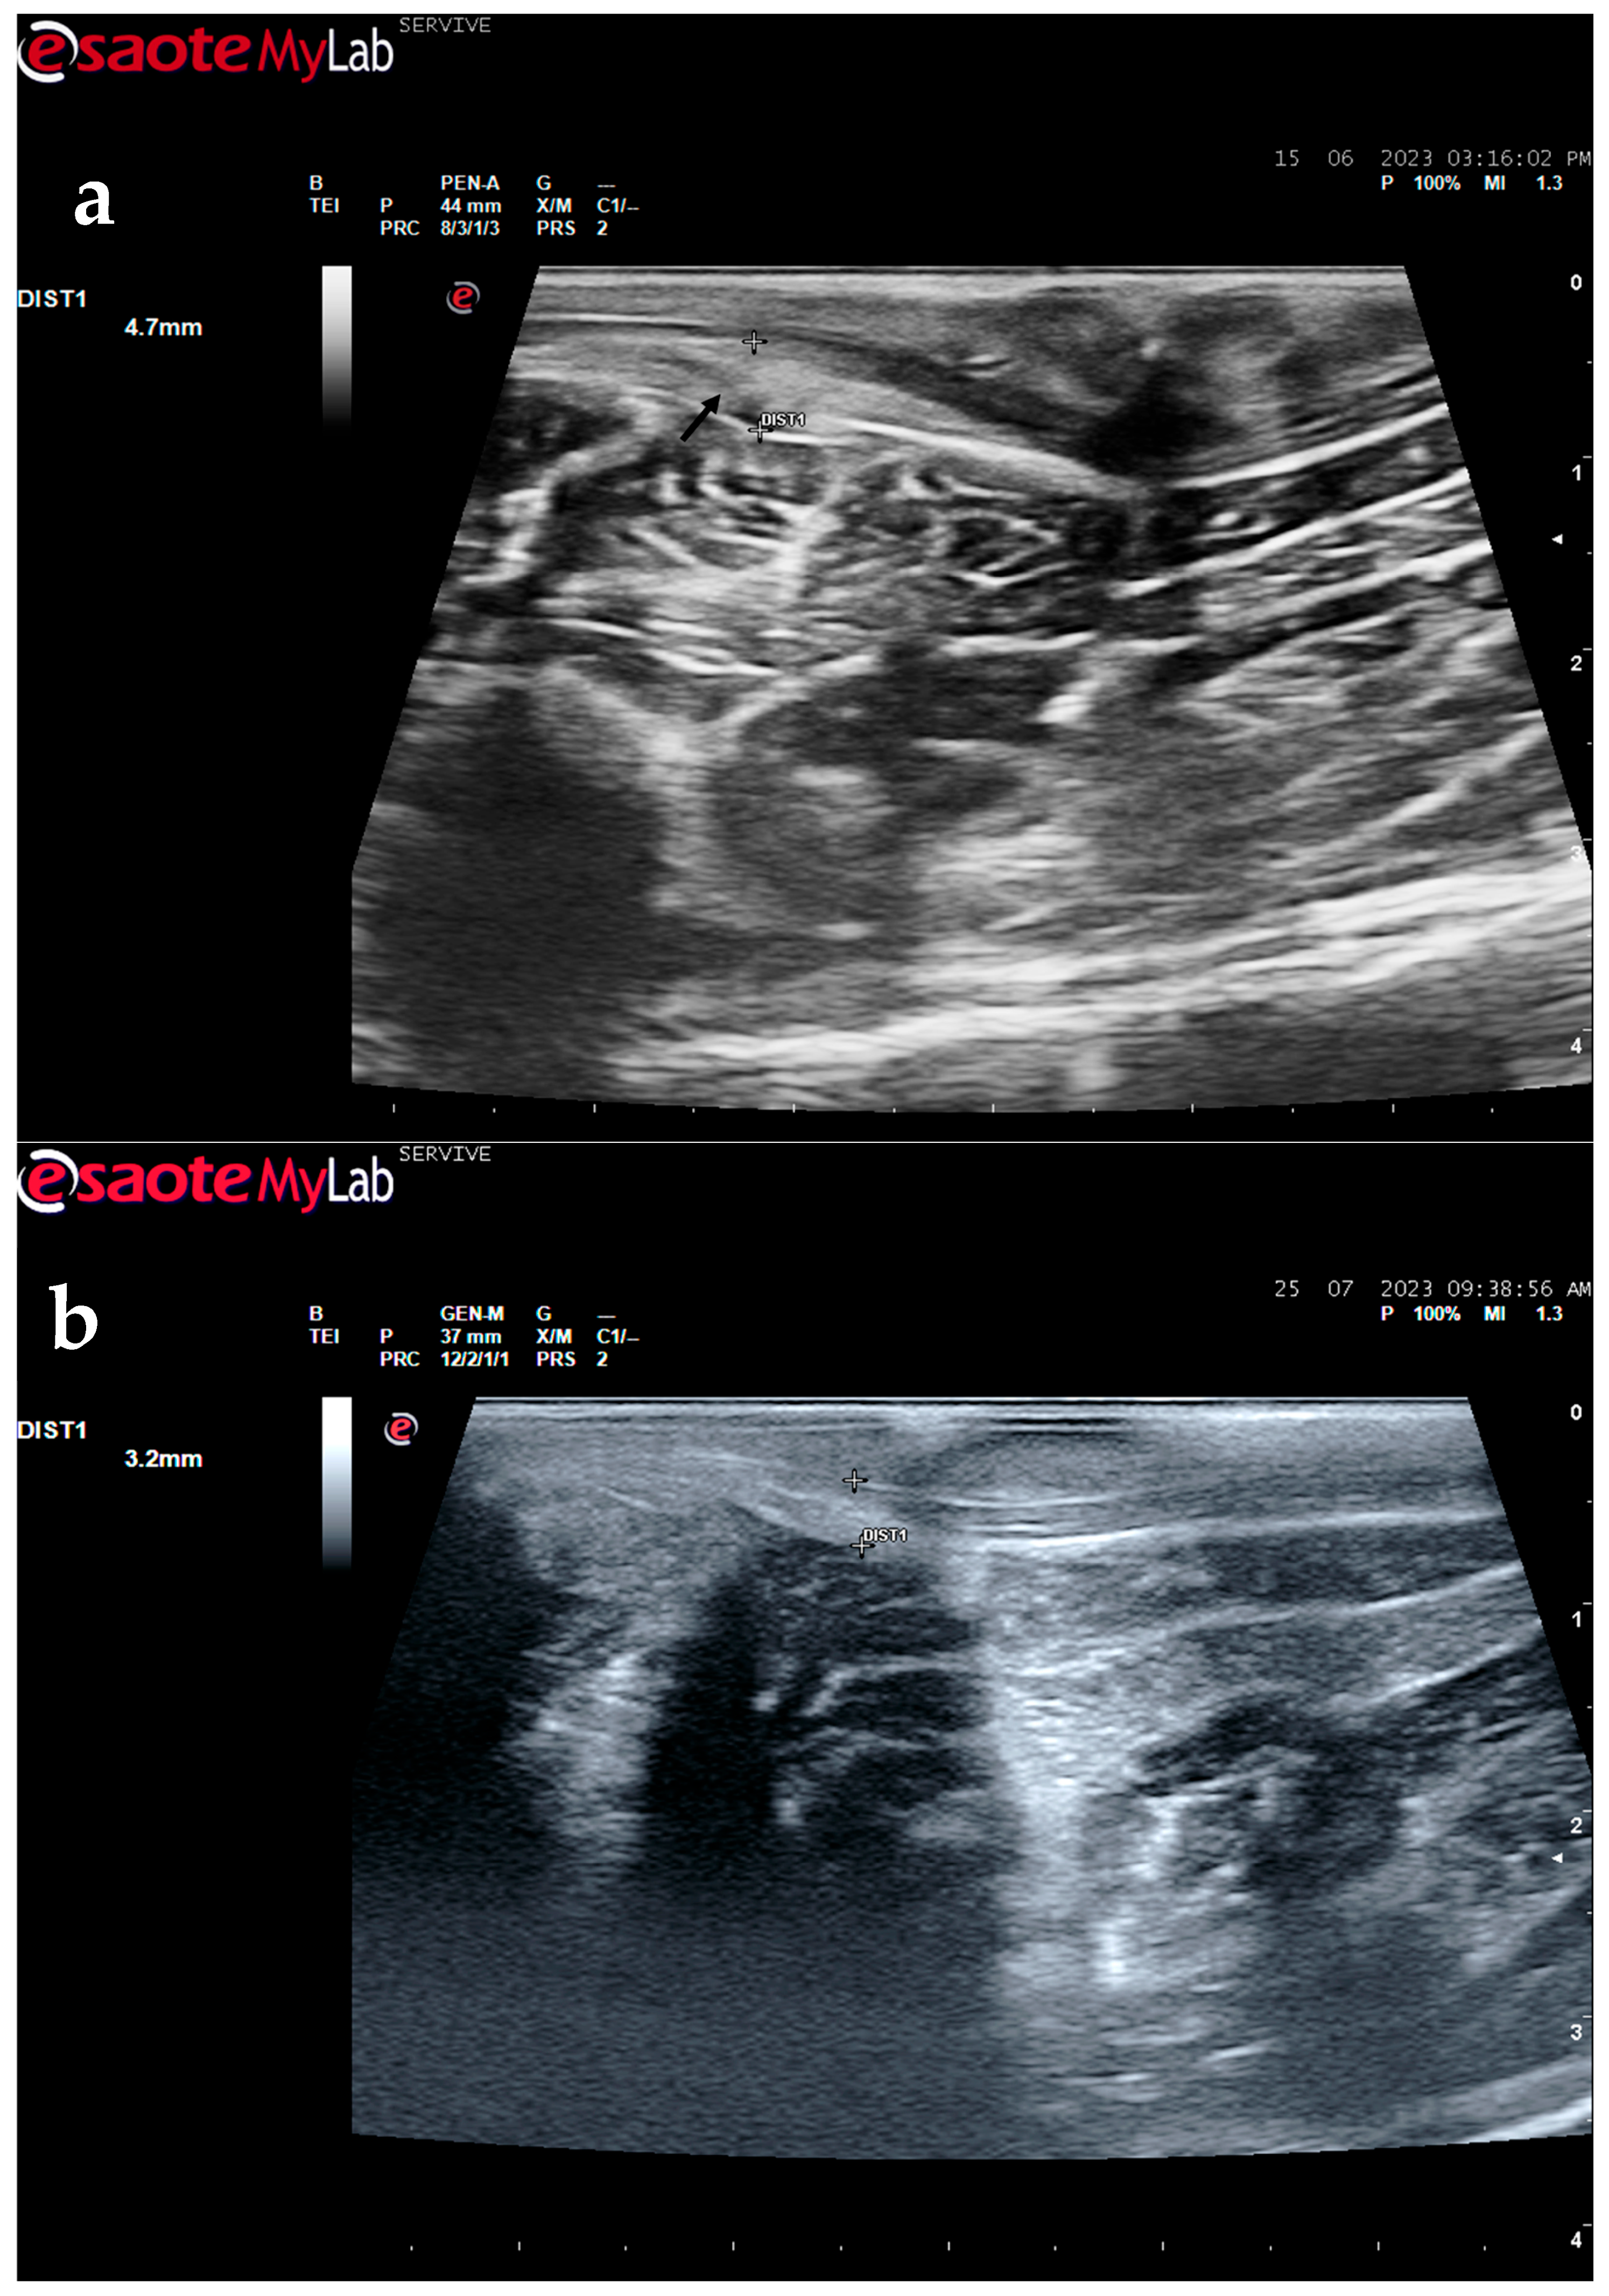

Figure 10.

Ultrasound image of the left peroneal nerve in a sheep subjected to a transection lesion followed by the application of an end-to-end suture. (a) After 1 week, it is possible to observe that the nerve continuity is still interrupted by a gap between the two nerve tops that have not yet fully reconnected (black arrow). DIST1 represents the nerve diameter, which is enlarged and with an increased hyperechogenic appearance due to interstitial edema and inflammatory infiltrate. (b) After 3 months, the nerve already presents an anatomical continuity, it is less hyperechogenic, and its diameter has decreased considerably (DIST1).